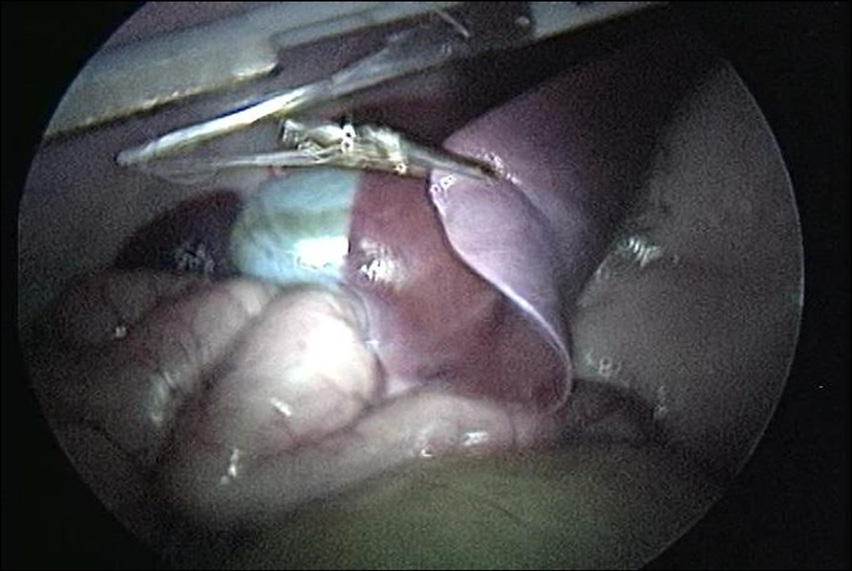

在内窥镜视野下,手动操作外部控制器,将LapR‐LMA拖动至肝脏附近。外科医生使用标准腹腔镜抓钳将鳄鱼钳 固定在肝脏的一个叶上。然后通过旋转驱动磁铁启动牵拉, 直至暴露肝脏下方的组织,如图17所示。该手术过程重复五 次,每次均改变LapR‐LMA的位置以及肝脏被抓钳固定的点。

手术过程结束后,动物被处死。位于腹壁组织的区域 LapR‐LMA在牵拉期间被固定,随后被切除并由专家病理学 家检查,报告显示由于磁力夹持导致的组织损伤迹象。